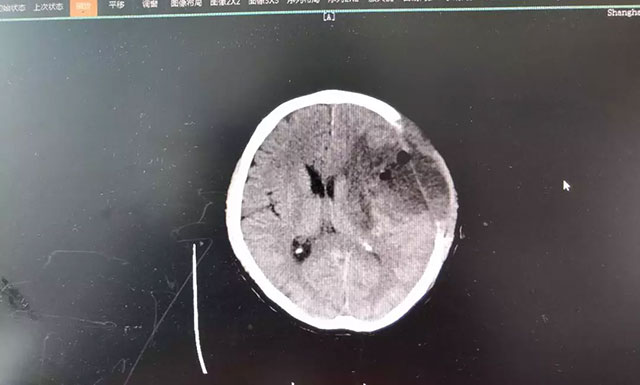

“是不是中风了?”家人看情况不妙,赶紧将钱先生送到当地医院检查。CT影像报告显示,患者大脑左颞叶占位。随后几天,钱先生的症状出现反复和恶化,考虑到当地医疗资源条件较为有限,家人将其转至上海蓝十字脑科医院,作进一步诊断治疗。